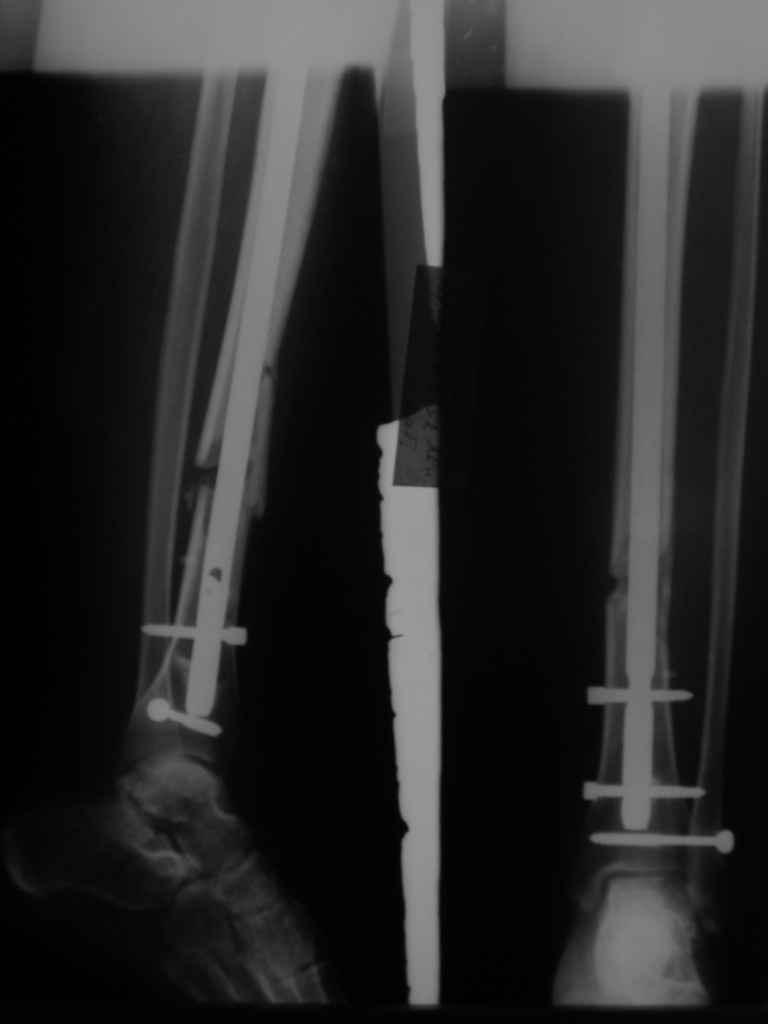

КА> Но почему решение динамизировать на сроке 8 недель с полным

В приложении картинка пациента со сломанным внизу гвоздем. Начал лечение в другом учреждении. Еще и адвокат к тому же.

Динамизировали через 8 недель, а оно поползло больше, чем хотелось бы.